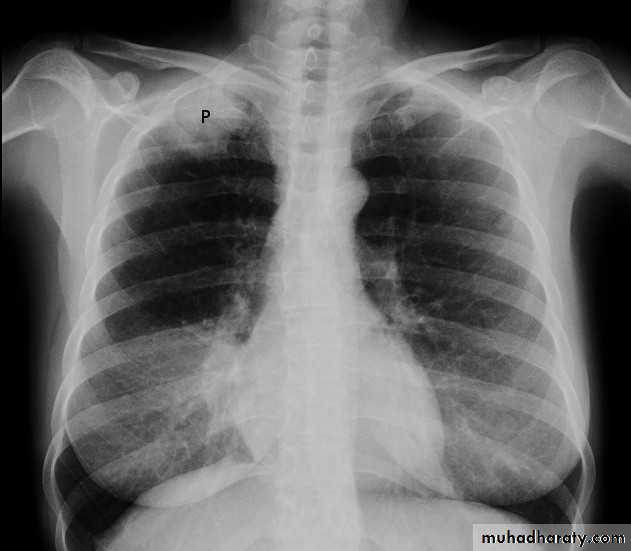

X-ray of pleural effusion

Massive right effusion